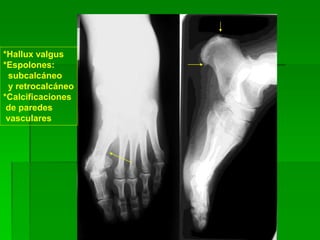

*Hallux valgus

*Espolones:

subcalcáneo

y retrocalcáneo

*Calcificaciones

de paredes

vasculares

Hallux valgus bilateral

Línea de Schade alterada

(hundida a nivel escafoideo-cuneiforme)

Ángulo del arco externo, aumentado

Pies planos bilateral